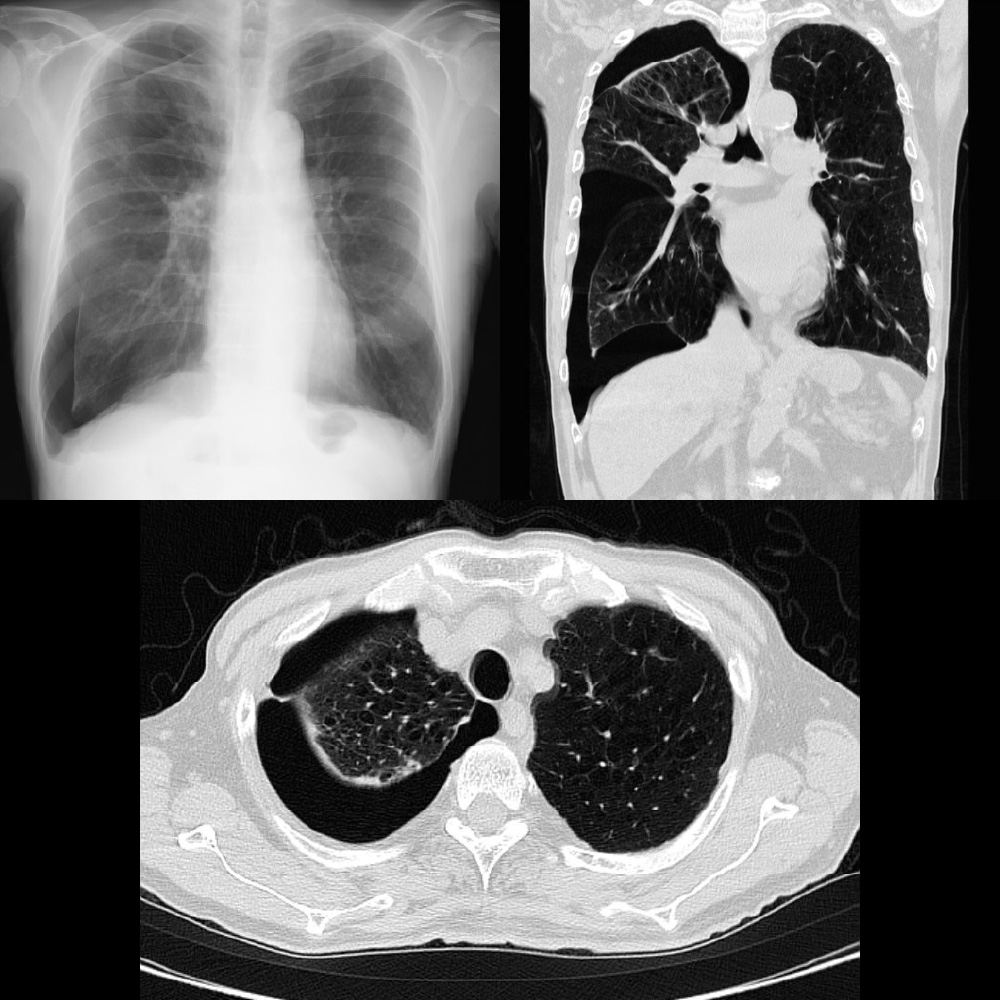

気胸

肺に穴があく、気胸 といわれる状態です。緊急に胸から空気を抜く必要があります。